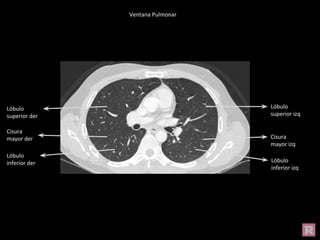

Ventana Pulmonar

Lóbulo superior

izq

Lóbulo superior der